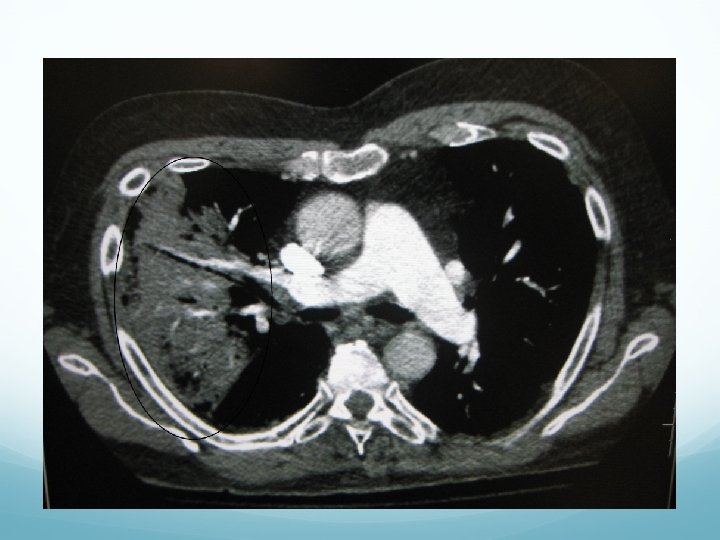

Which way is up?

What the $@#% is this? Which way is up? HUH?